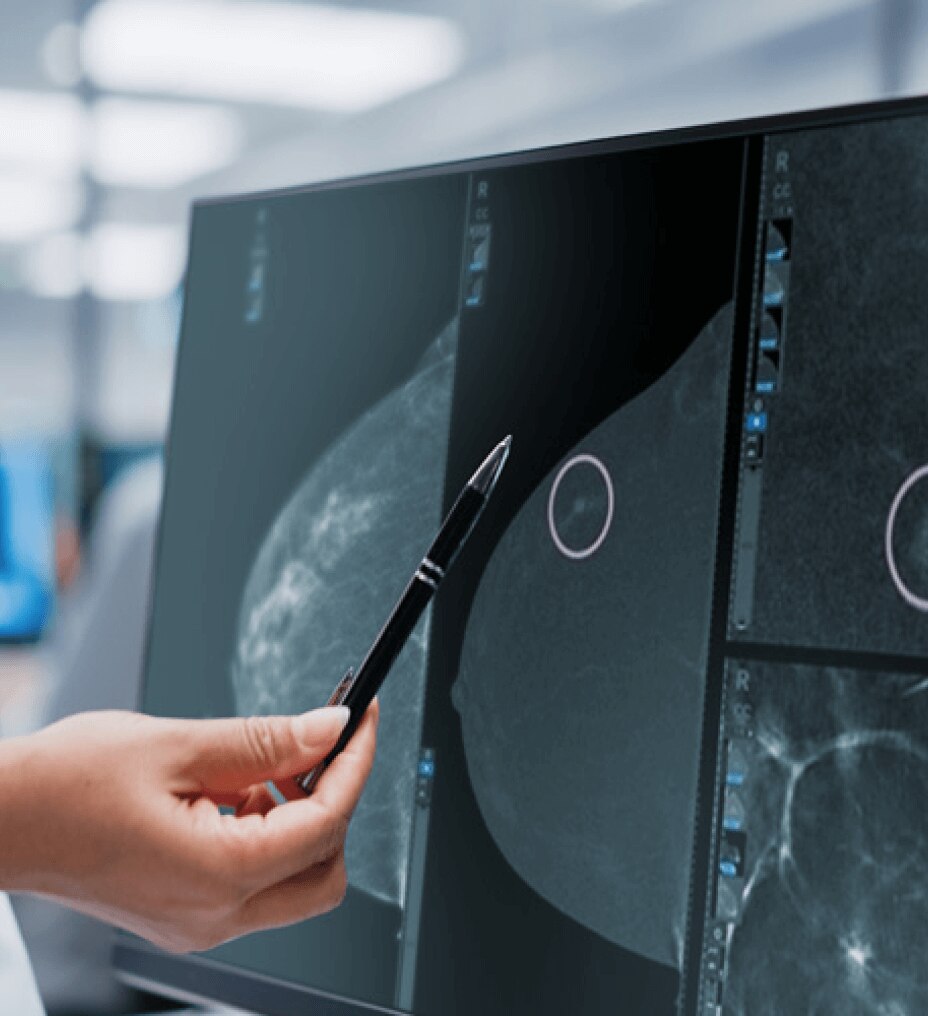

Optimize workflow to focus on what's important

ViewPoint 6 simplifies the way you work so you can focus on interpreting images rather than paperwork and reporting. By removing the need to dictate measurements from handwritten worksheets scanned into PACS, we help eliminate errors and enhance your workflow.